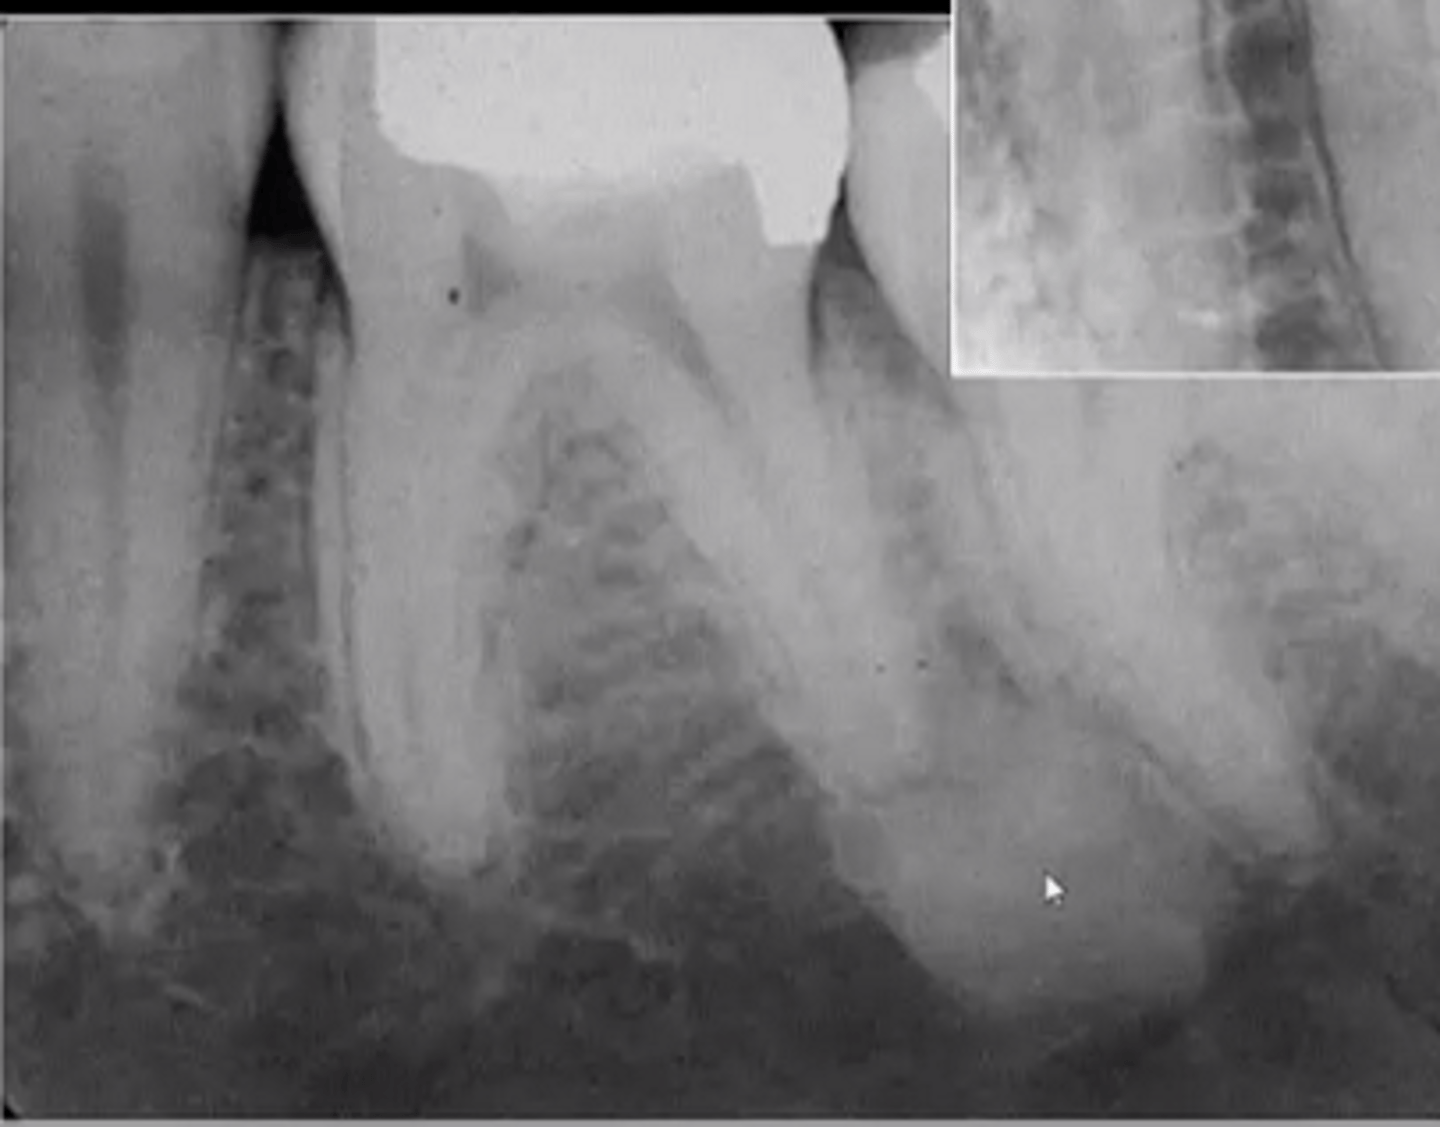

Radiographic Features of Diffuse Sclerosing Osteomyelitis

mixed

ill-defined

increased sclerotic bone

does not cross midline

shortening root